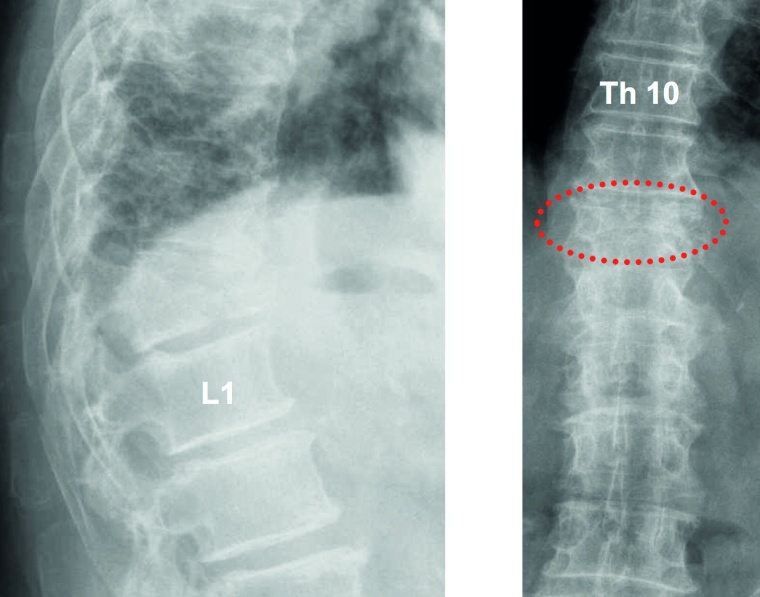

Fixateur interne: Haben die Osteolysen bereits Frakturen verursacht und weisen die betroffenen Wirbelkörper relevante Deformitäten auf, hat sich die perkutane überbrückende Stabilisierung mittels Fixateur interne bewährt (Abb. 2a und b). Der betroffene Wirbel kann ggf. additiv kyphoplastiert werden. Angesichts der sich zumeist anschließenden Radiatio verzichten wir jedoch zumeist darauf. Die Schrauben können je nach Knochenqualität zur Erhöhung der Stabilität wie üblich auch zementaugmentiert werden.